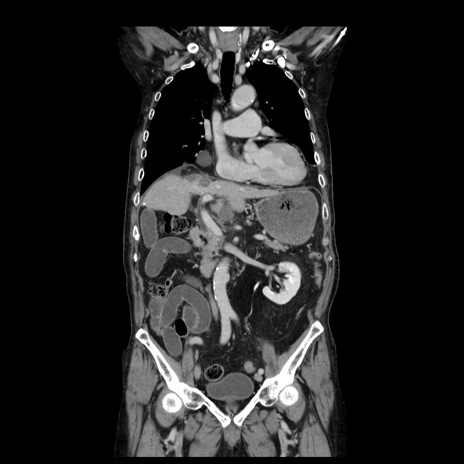

横断像

【症例】70歳代男性

【主訴】腹痛

【現病歴】肝硬変・肝細胞癌にてかかりつけの方。約9時間前に食後より腹痛出現。症状が徐々に増悪し、嘔吐出現したため来院。

【既往歴】肝硬変、肝細胞癌(RFA、TACE後)

【身体所見】意識清明、表情苦悶様、BT 36℃、BP 129/78mmHg、P 88bpm、SpO2 97%(RA)、右上腹部から心窩部にかけて圧痛あり、反跳痛なし、筋性防御あり。

【データ】WBC 5800、CRP 0.16